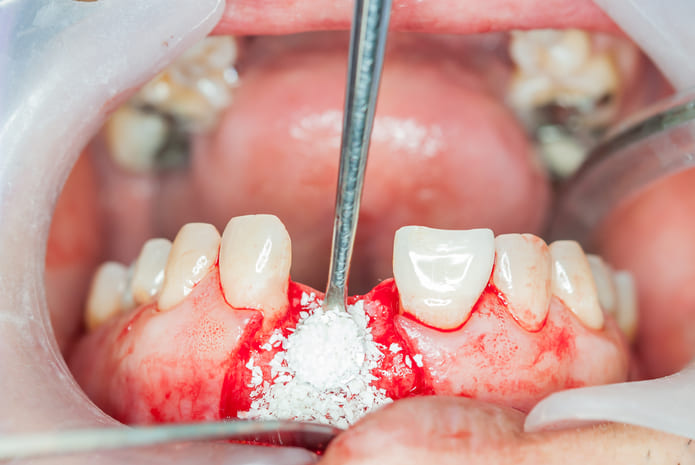

En el caso de la regeneración ósea guiada, se coloca un biomaterial normalmente en forma particulada y se recubre con una membrana para evitar que los tejidos blandos interfieran en la cicatrización del hueso.